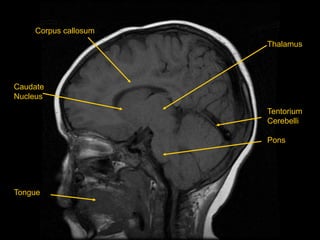

Corpus callosum

Thalamus

Tentorium

Cerebelli

Pons

Caudate

Nucleus

Tongue